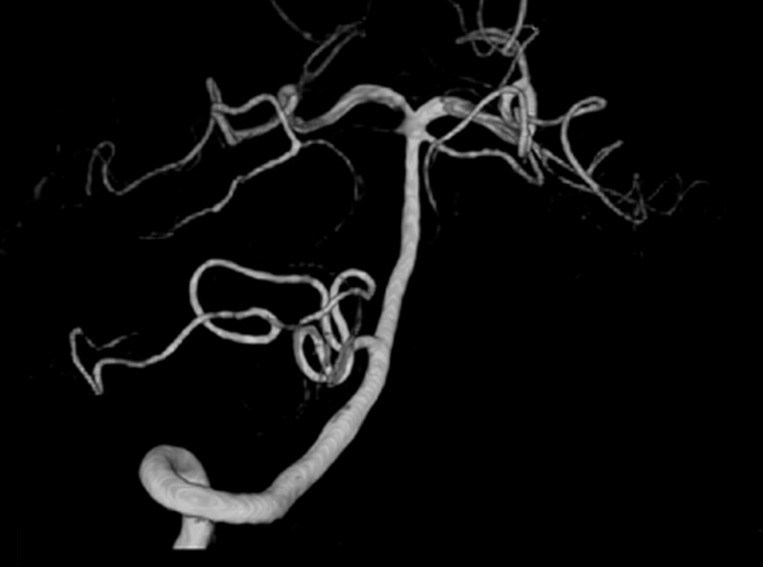

Fig. 2) to identify any intracranial aneurysm that might be present (

Fig. 3), and 3) results of immunoblot analysis for antibodies against 21-or 24-kDa antigen band of

Fig. 3Three-dimensional digital subtraction cerebral angiography (DSA), lateral view of internal carotid artery and anterior cerebral artery showing subarachnoid hemorrhage from aneurysm at anterior communicating artery.